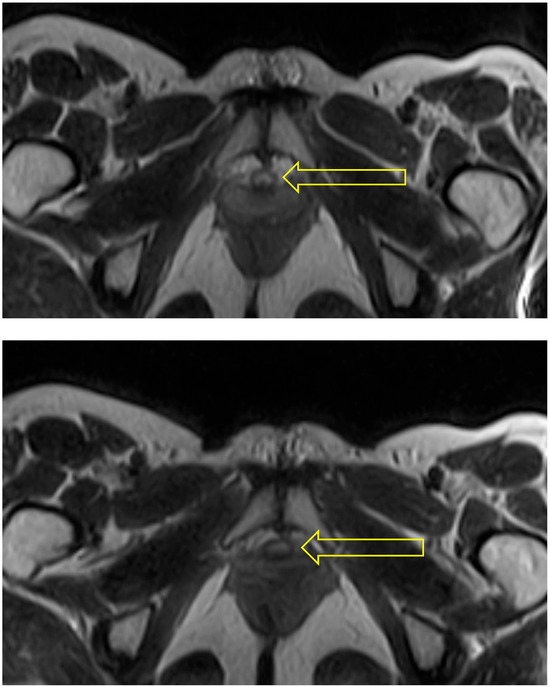

In the squat pose, Malasana, the urethra was seen as a circular structure at the bladder neck, but to be become oval in shape in the region of the mid-urethra (see Figure 4).

Figure 4. Squat: The two scans selected from this sequence show the urethra (indicated by arrow) as a circular (uncompressed) structure at the bladder neck (upper) and oval in shape and hence probably compressed at mid-urethra (lower).